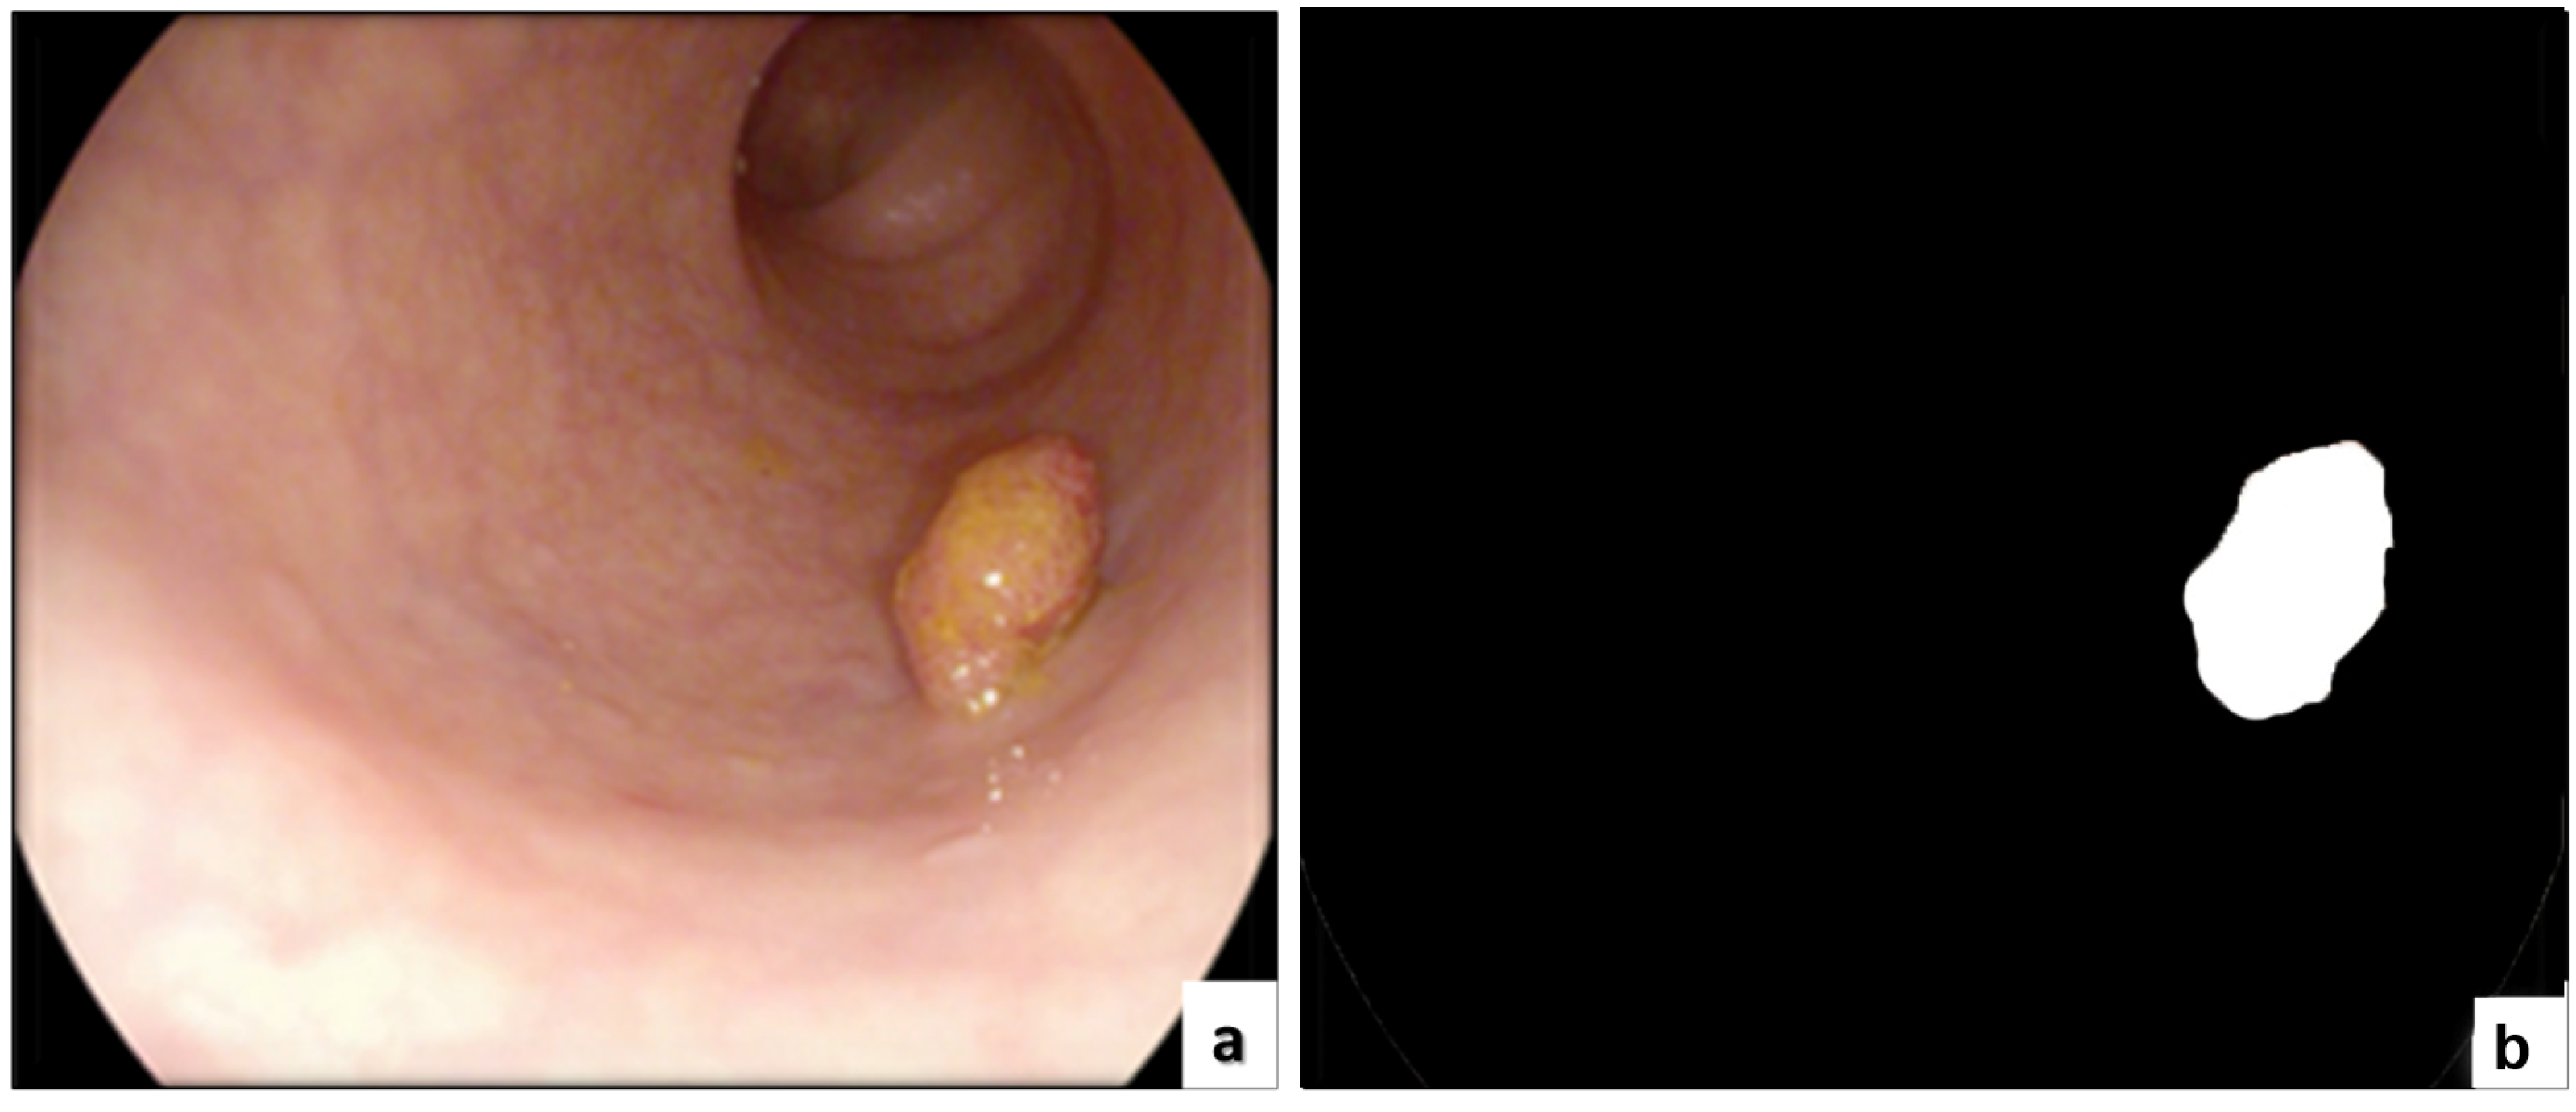

3.1.1. Virtual Computed Tomography Colonoscopy (CTC)

3.1.2. Magnetic Resonance Imaging (MRI) and Endorectal Ultrasound (ERUS)